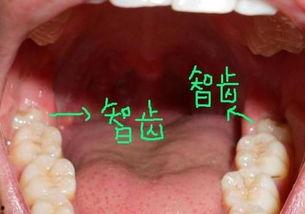

首先,得先了解一下智齿。智齿,学名第三磨牙,是人类口腔中最后长出的牙齿。它在青春期到成年早期之间长出,因此得名“智齿”。不过,由于现代人的饮食结构和生活习惯的改变,智齿往往没有足够的空间生长,导致各种问题。

1. 智齿阻生:这张图片展示了一颗阻生智齿,可以看到它顶住了旁边的牙齿,导致牙龈红肿。